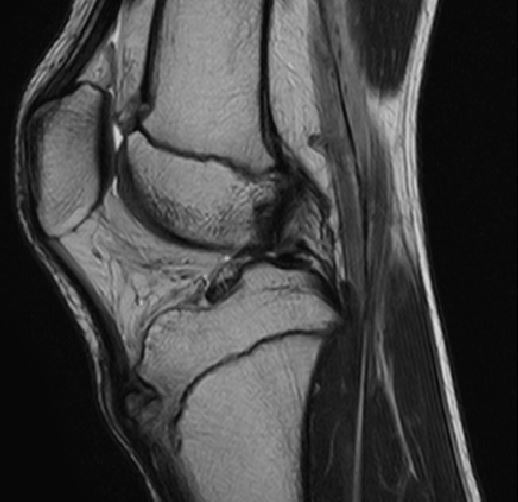

視診、触診、単純レントゲン検査で診断可能です。MRI検査では脛骨粗面、周囲の炎症の状況を確認します。

脛骨粗面周辺に信号変化(炎症所見)

脛骨粗面に遊離骨片